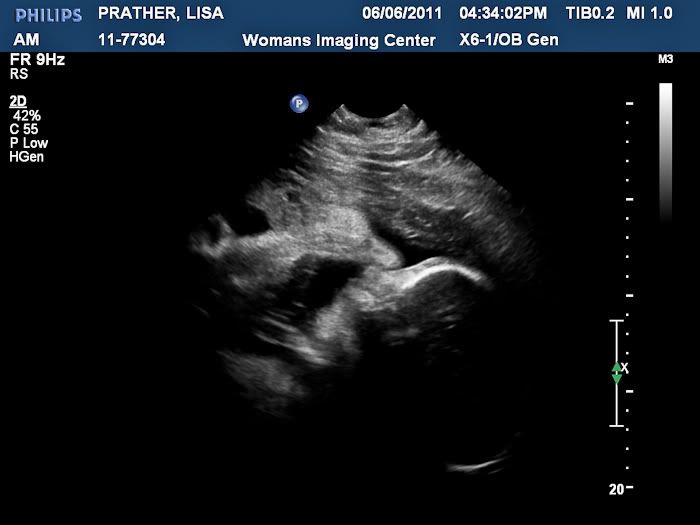

We had an ultrasound today and got to see our baby boy! It was so wonderful to see him, but even better to find out that he is still perfect. He weighs 4 pounds and 11 ounces right now!

Another shot of his face:

Here is a profile shot. You can see one hand up by his face. Both hands were up by his face pretty much the whole time until the end when we decided to stretch his legs by nearly kicking himself in the face!

The ultrasound technician said he had lots of hair. No wonder I've been having such bad heartburn.